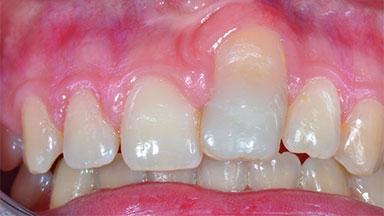

In 2008, a healthy 15-year-old female, non-smoking patient presented at our clinic with a major esthetic problem of tooth 21. Her dental history revealed that the tooth had been avulsed by trauma years before. As a result, the replanted and temporarily splinted tooth had ankylosed and was in severe apical malposition. The ankylosed tooth exhibited a significant gingival recession that disturbed the patient greatly. Due to the patient’s low age and with her skeletal growth not completed, periodic follow-up visits were scheduled to monitor the situation until the patient was old enough for implant therapy.